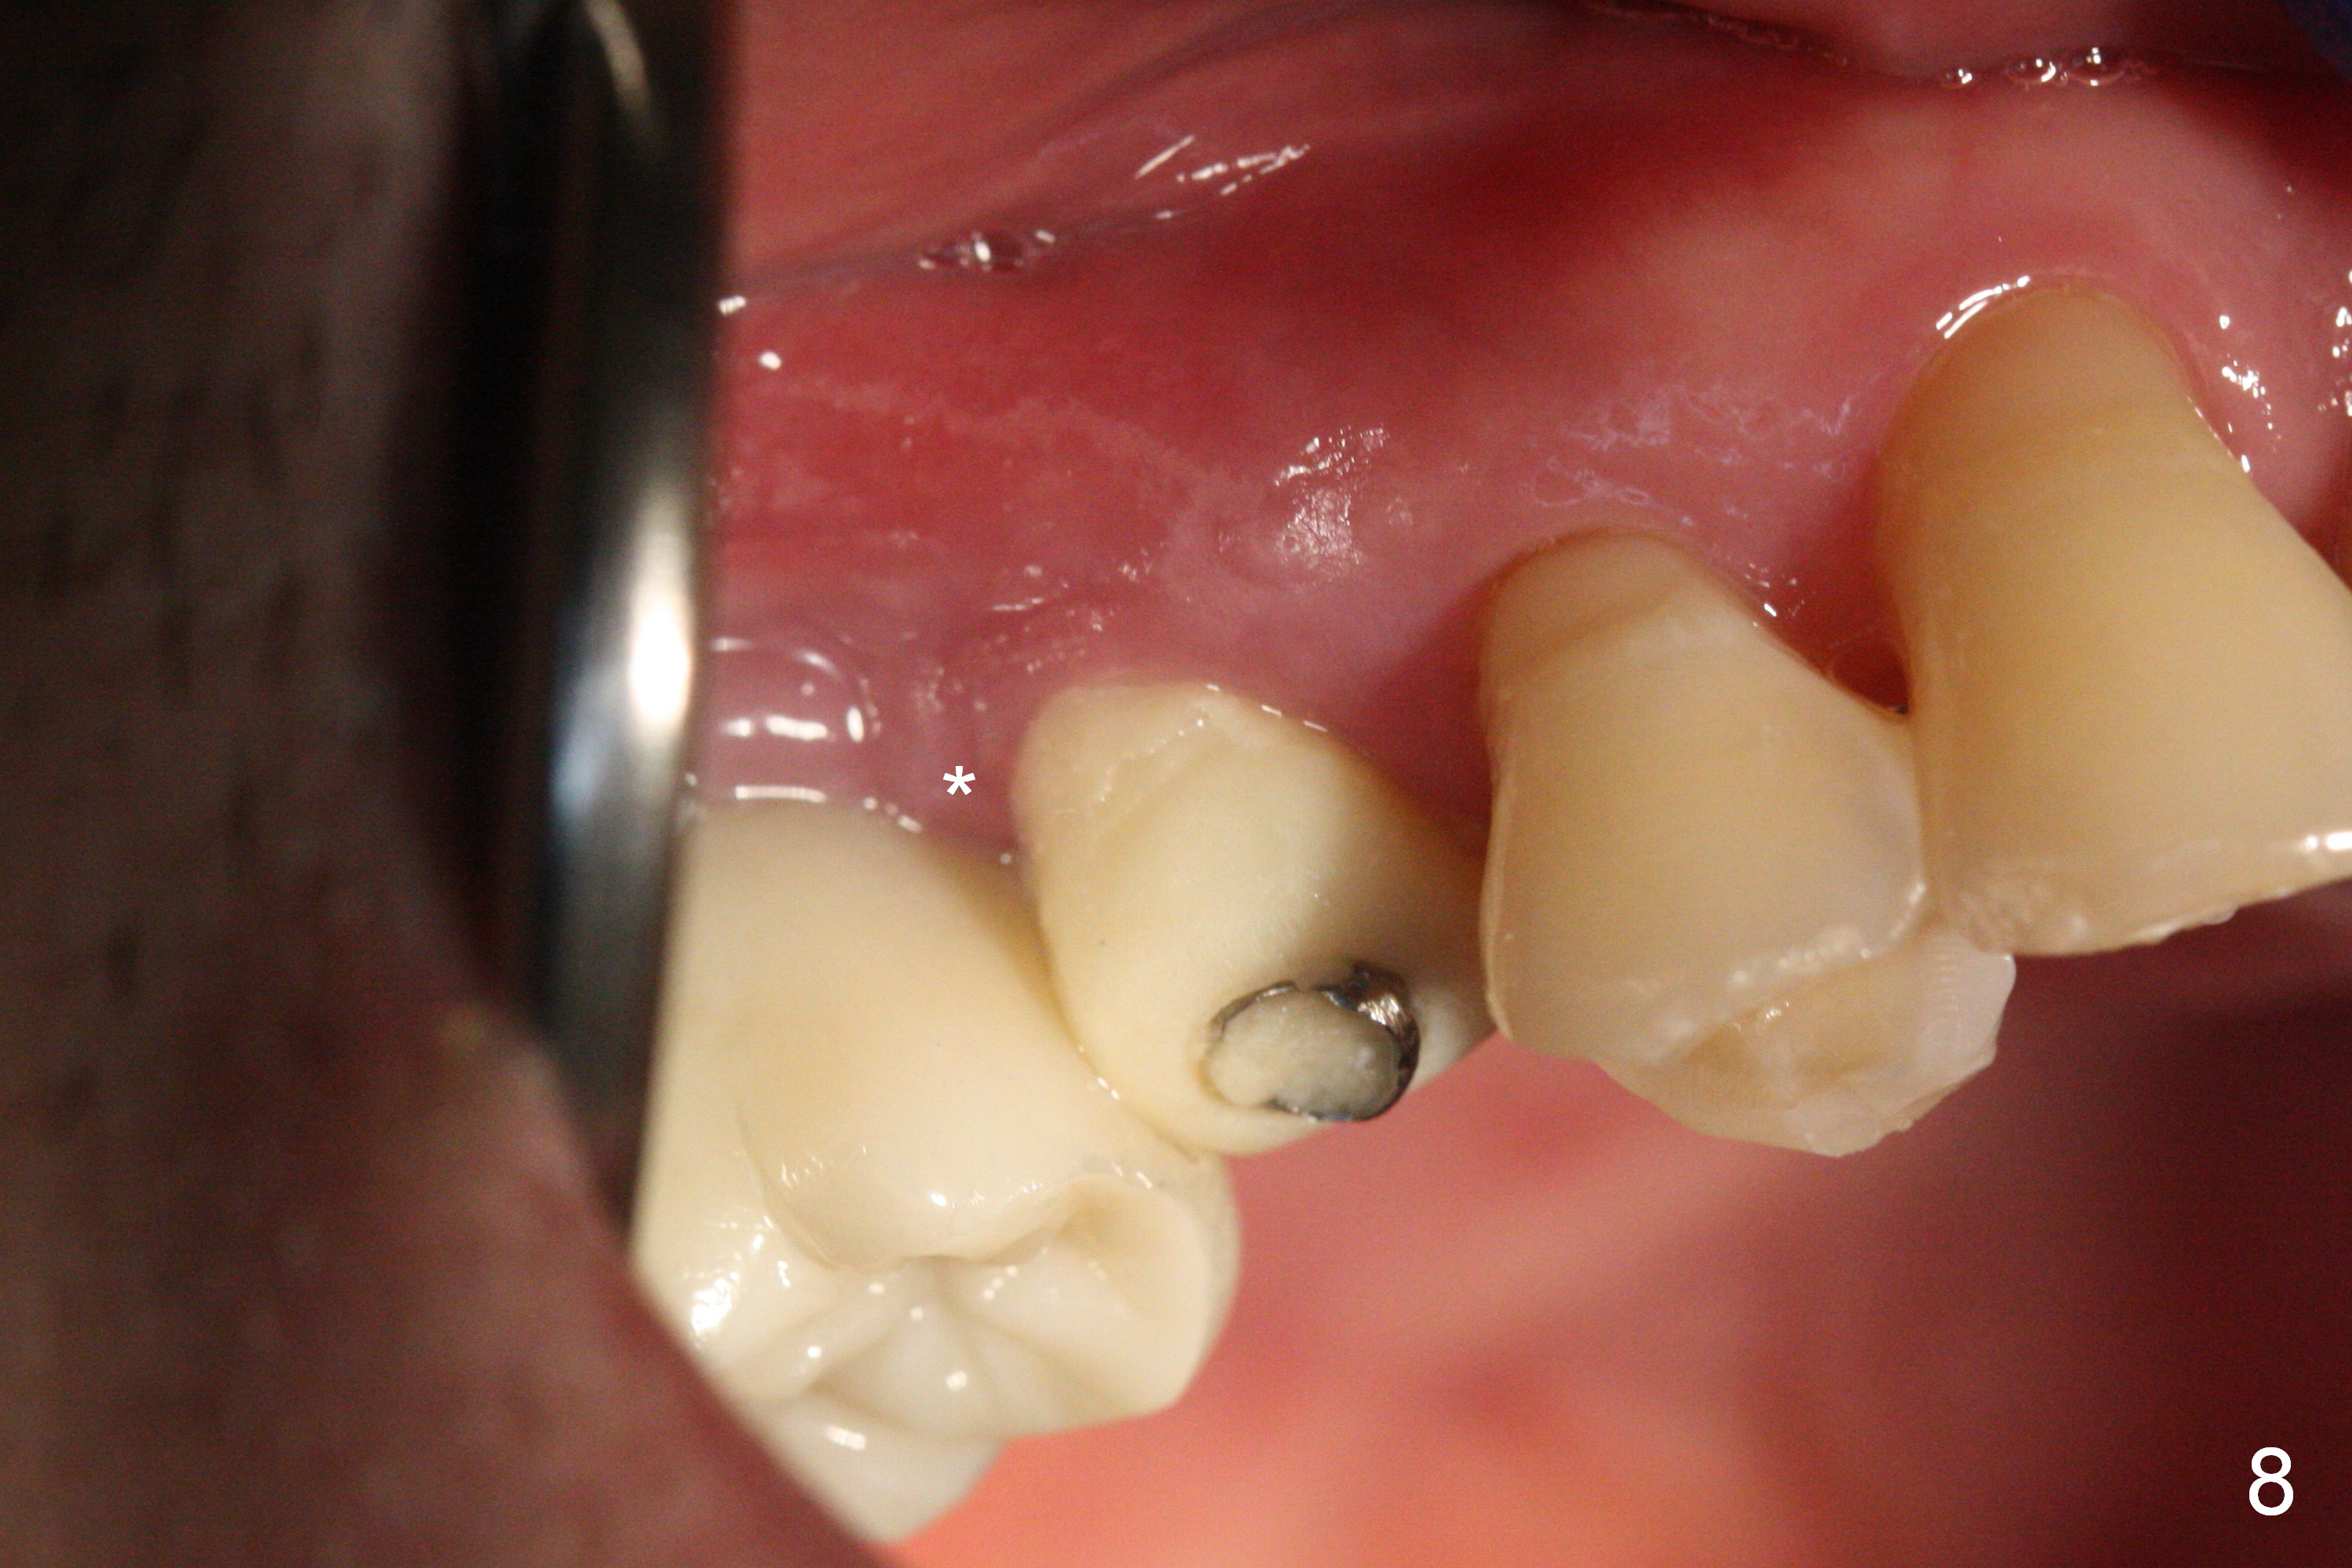

The distal papilla reforms buccally (Fig.8 *) and palatally (Fig.9) 4 months postop.  It appears that the 4 mm cuff of the pair abutment (Fig.10 >) is apical to the mesial crest (*).  The distal coronal implant threads seem to be covered by bone graft (Fig.11 <).  Therefore pair abutments with 5 mm or more cuff are required in cases of the uneven bone.   Implants have to be placed deep.  CT taken 3 months post cementation (10 months postop) shows that the implant is placed in the middle of the alveolus without apparent thread exposure.  CT taken 1 year and 8 months post cementation (Fig.13) shows that the implant is placed in the middle of the alveolus without apparent thread exposure, as compared to those at #2 and 3, which are placed buccal (B).